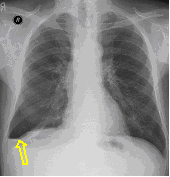

23. Pulmonary metastases, bidirectional (PA and right lateral) plain chest radiograph.

51 year old woman, endometrial carcinoma. Numerous ring shadows bilaterally in basal dominance (max. appr. 12 mm). Left pleural effusion of one finger wide.